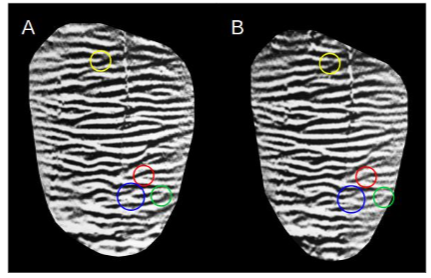

The steps used in image filtering and binarization were: 1. The image with highlighted HSB with the useful region selected has its edges removed. 2. Global orientation adjustment. 3. Resizing according to the estimate of the average frequency of the bands (adapted from Hong et al.). 4. Vertical filtering. 5. Binarization with equalization of the white/black ratio. 6. Smoothing by resizing. 7. Filtering of local pixels using Gabor filter in an iterative mode. This last step is performed gradually with three repetitions, established after visual comparisons of the HSB pattern between the input and output images, to balance both filtering quality and fidelity. Increasing repetitions improves the filtering quality at the expense of the HSB fidelity of the input image. Some examples of results obtained with the filter flowchart are presented in Figure 3.

Feature extraction from filtered HSBs is quite similar to the process used in fingerprints. The main features used are terminations and bifurcations. These minutiae are identified after skeletonization of the binary image. In this process, the bands are reduced to the thickness of a single pixel, while maintaining their extension. Thus, it is possible to map regions whose number of neighboring pixels is equal to one for terminations and equal to three or more for bifurcations. As a result, many false minutiae were found. Post-processing to remove false minutiae is applied using several techniques, including adaptations of. Due to the variations in illumination of the initial photograph, there is ambiguity in determining the type of minutiae found: termination or bifurcation? An example is illustrated in Figure 5. To solve this problem, we considered only terminations, but for both light and dark bands. In this way, a larger number of minutiae can be compared.